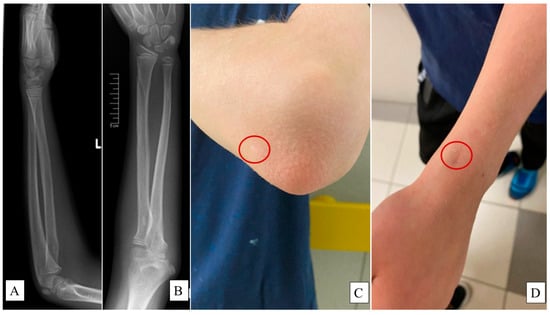

X-rays were employed to assess the remodeling of the bones (Figure 4A,B), while surgical scars were evaluated using the Vancouver Scar Scale (VSS) (Figure 4C,D) [26], calculating the composite score of four criteria:

Figure 4. X-rays captured at the one-year follow-up examination of a L pediatric forearm fracture treated with PLGA implants from lateral (A) and AP (B) views showing intact bone growth and development. Surgical scars—highlighted by the red circles—were evaluated via the Vancouver Scar Scale (VSS) on the olecranon ((C), 0 point) and the distal end of the radius ((D), 1 point).